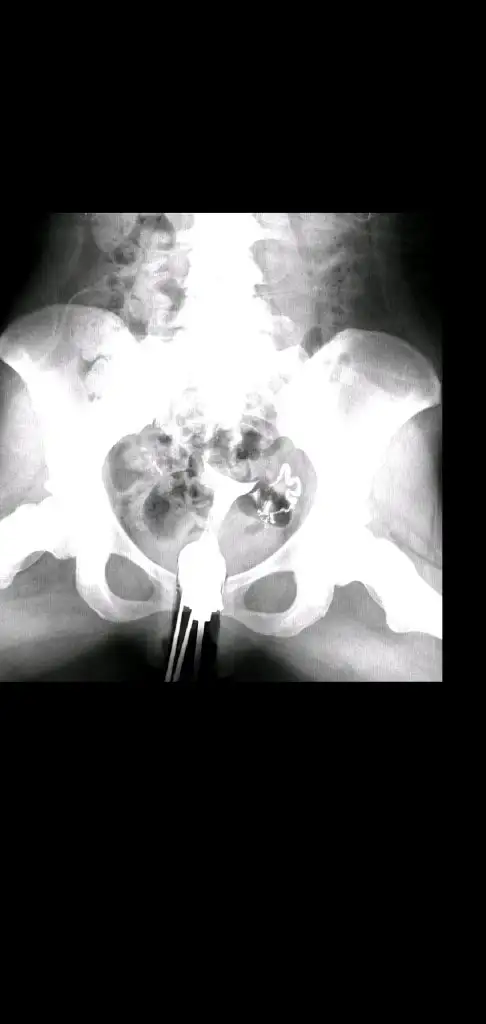

Canım bak 2 ve 3 ilk vuruşlardaki hali en baştaki de 4. Vuruştan sonra çekilen görüntü. Geçiş görünüyor ama açıldı mı bilmiyorum. Doktor lap a gerek yok şuan dedi. 4 ay sonra bi daha hsg çekilcem kendi isteğimleCanım senin tüptekş yapılıklık rahim gilmi ile açıldı mı peki?

Geçiş varsa açılmıştır kuzumCanım bak 2 ve 3 ilk vuruşlardaki hali en baştaki de 4. Vuruştan sonra çekilen görüntü. Geçiş görünüyor ama açıldı mı bilmiyorum. Doktor lap a gerek yok şuan dedi. 4 ay sonra bi daha hsg çekilcem kendi isteğimle

Umarım canım valla çoğu doktor sıkıntı yok yapışıklık varmış açılmış diyor instada bi kadına attım o da tam peritonel geçiş yok gibi falan dedi ama ben yine aşılamadan önce çekilcem hsg bi son hali ne durumda göreyimGeçiş varsa açılmıştır kuzum![]()

Açılmış canım geçmiş sıvı karın boşluğuna iki taraftan daCanım bak 2 ve 3 ilk vuruşlardaki hali en baştaki de 4. Vuruştan sonra çekilen görüntü. Geçiş görünüyor ama açıldı mı bilmiyorum. Doktor lap a gerek yok şuan dedi. 4 ay sonra bi daha hsg çekilcem kendi isteğimle

Umarım canım ben de öyle düşünmek istiyorumAçılmış canım geçmiş sıvı karın boşluğuna iki taraftan da